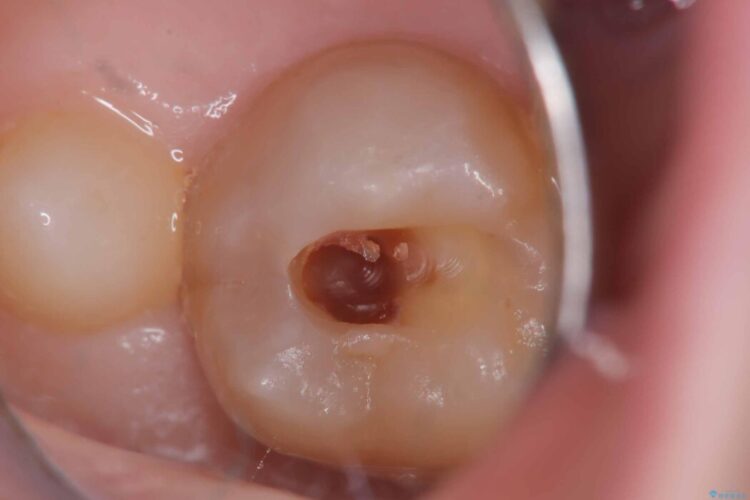

以前に詰めた白い詰め物の内部で、虫歯の再発が確認されました。

まずは古い詰め物と虫歯を丁寧に除去します。